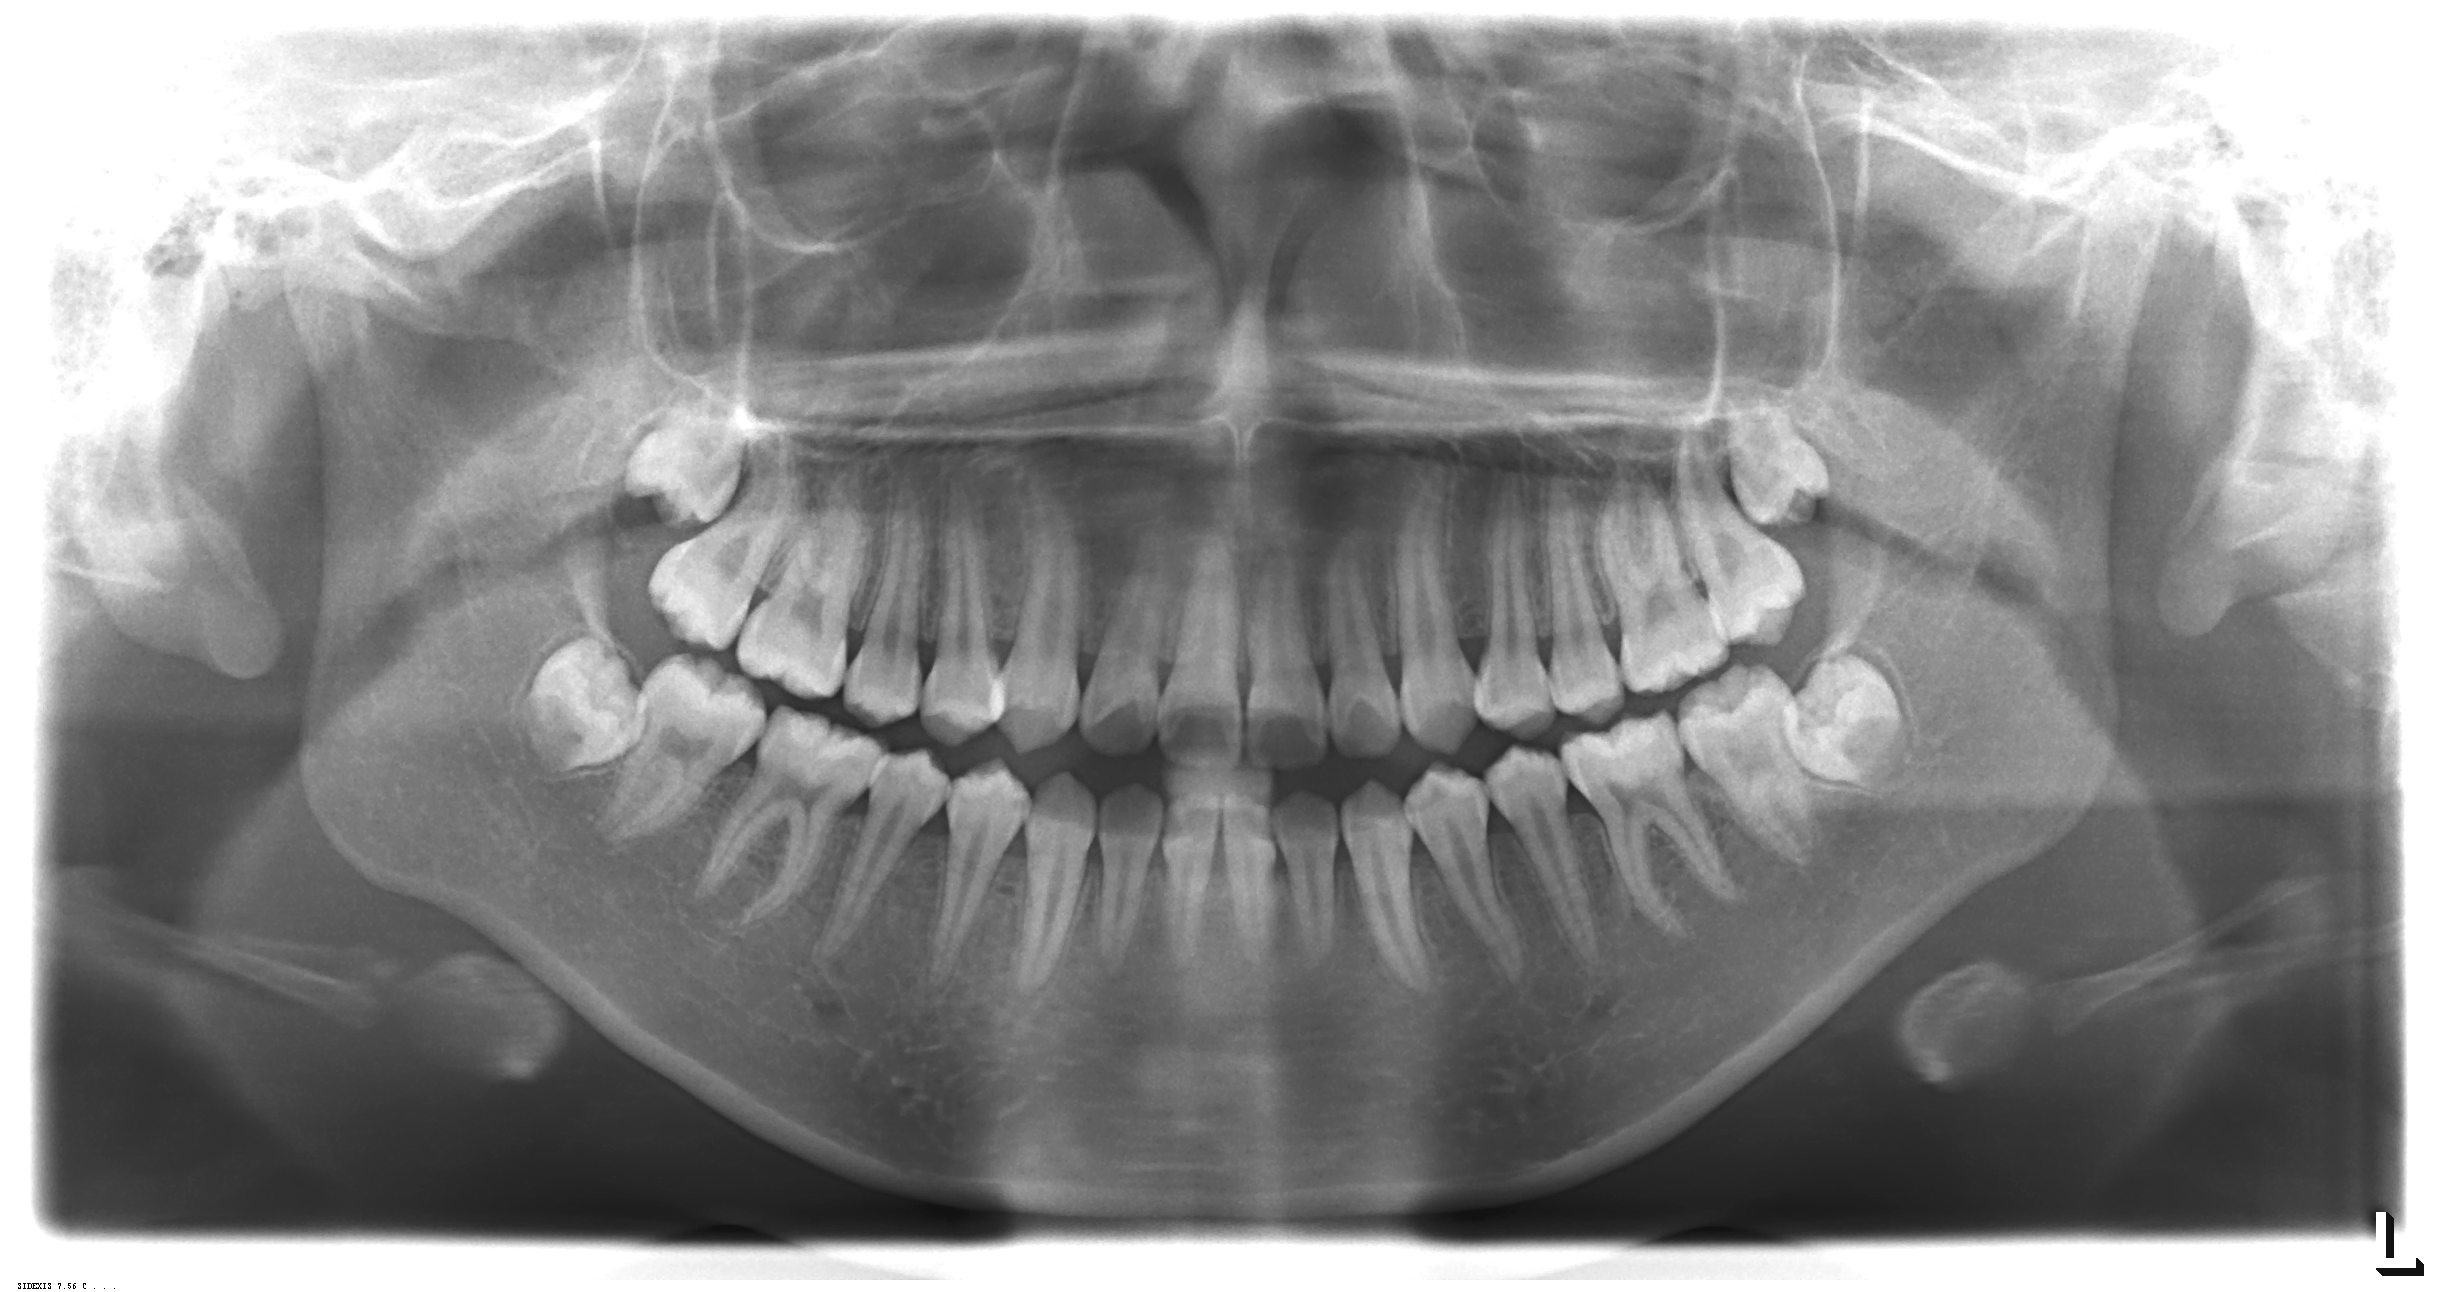

2、数字化口腔全景机:可拍摄口腔全景片、头颅定位测量片、颞下颌关节片及头颅后前位片、瓦特氏位片等。